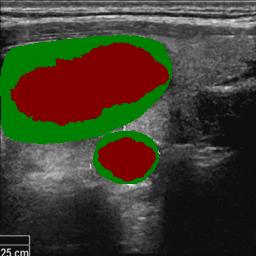

3.4.3 Prototype Correlation Loss for Boundary-level Shape Learning

To learn pixel-wisely precise segmentation shapes, building on the segmentation objective defined as Eq. (3), we extend the shape constraint to boundary-level by introducing a prototype correlation loss, to make the uncertain pixels on the classification boundary in the feature space closer to their category prototypes.

As illustrated in Fig. 4, given the high-confidence foreground and background labels and , we first extract the corresponding region features and . The foreground/background prototype and is obtained by extracting deep features located in regions of the high-confidence foreground/background labels and performing average pooling, where means feature channels.

| (10) | ||||

Using metric learning, we evaluate the correlation response of each position in the feature map with respect to the foreground prototypes and background prototypes, obtaining the foreground correlation response and the background correlation response as follows:

| (11) | |||

Since foreground and background are mutually exclusive in segmentation tasks, the foreground correlation response can be derived from the background prototype as follows:

| (12) |

The correlation map represents the similarity between image features and each prototype. The first component of the prototype correlation loss reflects the complementary consistency between the feature correlations referring to high-confidence foreground and background prototypes, which is defined as follows:

| (13) |

The fused predictions are obtained by balancing the foreground correlation maps based on the foreground and those on the background prototypes.

| (14) |

The second component of the correlation loss that measures the consistency between the fused correlation map and the segmentation prediction is defined as:

| (15) |

The total prototype correlation loss is then calculated as follows:

| (16) |

By considering the complementary consistency of foreground and background prototype correlation, the algorithm obtained segmentation edges with low uncertainty. By directly propagating the fused segmentation boundaries to the predicted results, we achieve explicit shape learning, effectively addressing the challenge of refining the boundaries of nodule regions.